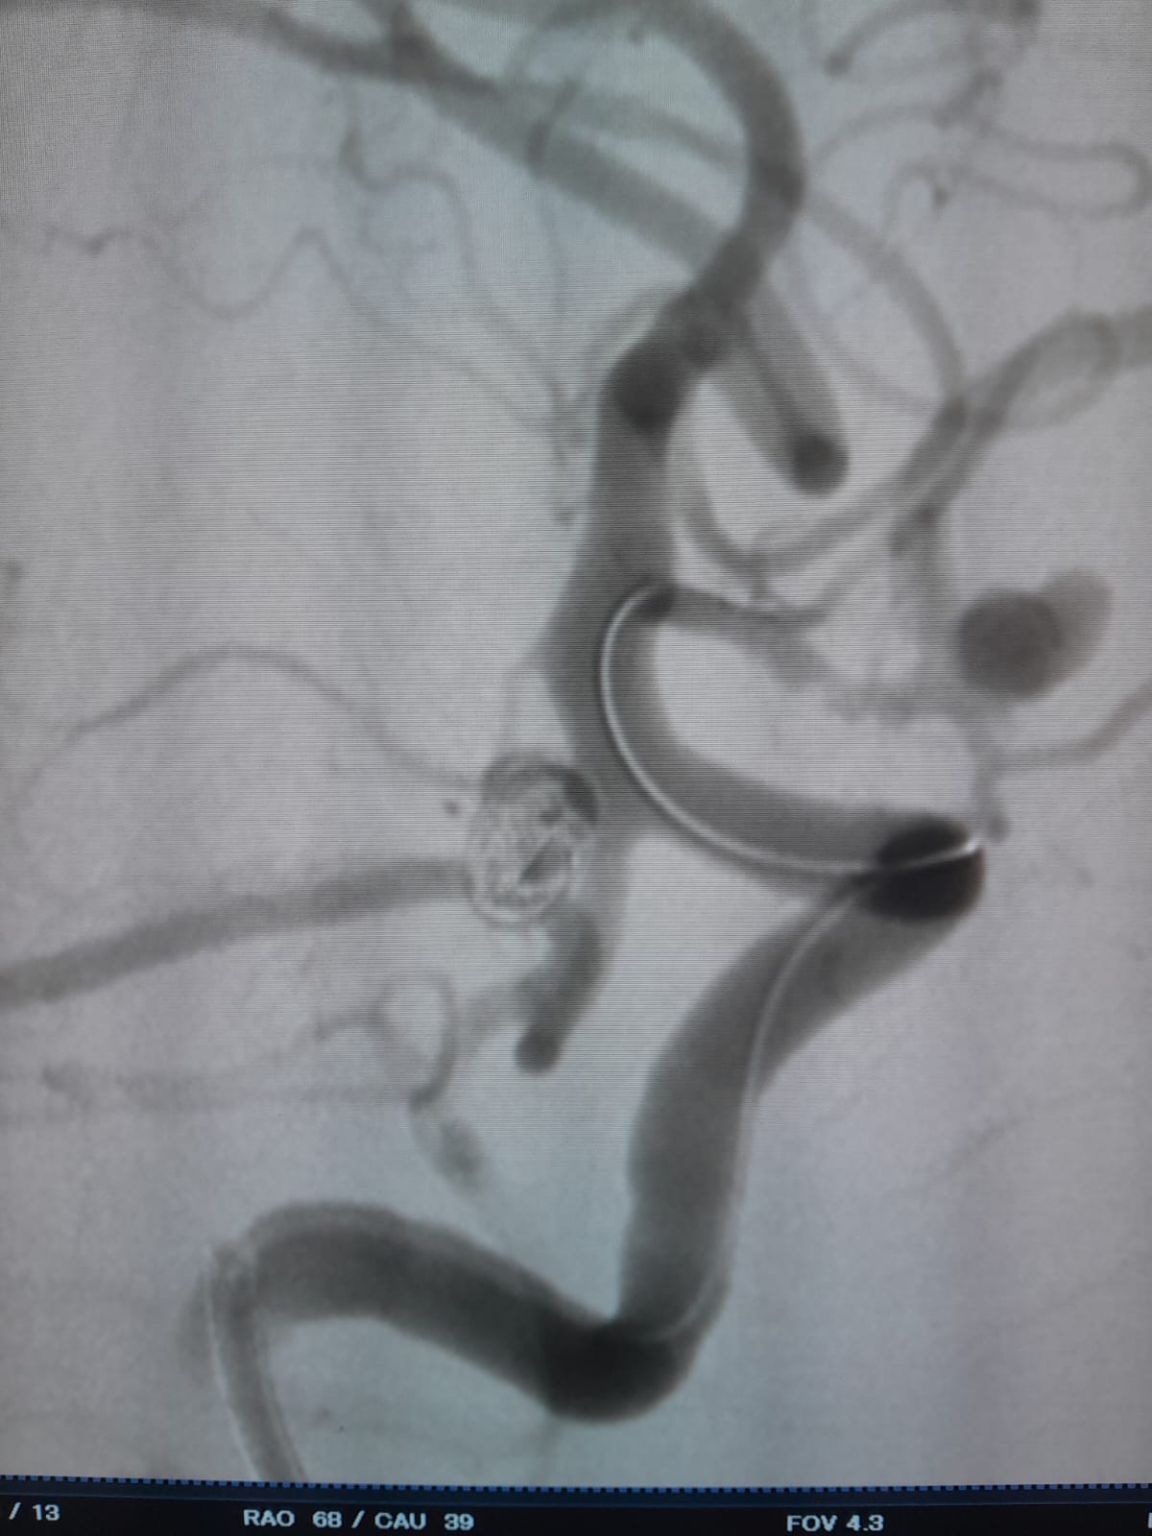

Ustanowiono dostęp naczyniowy, a następnie zespół z powodzeniem przeszedł przez Frepass®Jednorazowy mikrocewnik (TJMC14) do miejsca docelowego. Embolizację przeprowadzono przy użyciu trzech Perdenser®Embolic Coil System (TJCST4.508-3D, TJCST0306-3D, TJCST0206-3D) wdrożony wraz z Deromper®Kontroler odłączenie cewki (TJCDC).

Podczas obserwacji odnotowano wypełnienie szczątkowe w wcześniej leczonym tętniaku tętnicy łączącej tylnej. Zespół ponownie uzyskał dostęp do witryny za pomocą Frepass®Jednorazowy mikrocewnik (TJMC18 Plus) i pomyślnie wdrożył Nuva®Flow Diverter (TJED-D-4.5-16), który wykazał idealną przyłożenie do ściany i doskonałe przekierowanie przepływu, co prowadzi do bardzo zadowalających wyników leczenia.